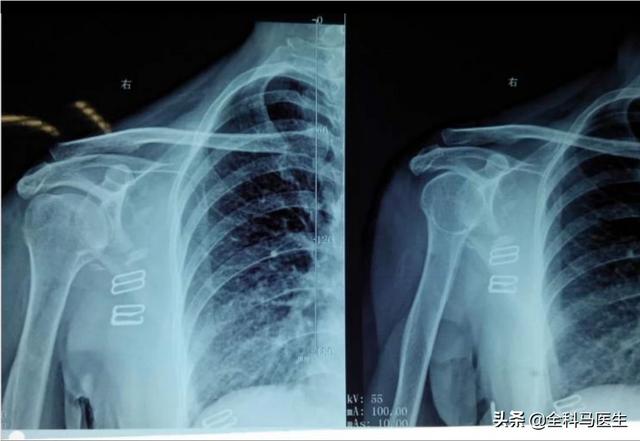

1、Eingefrorene Schulter oder Muskelzerrung der rechten Schulter und des Rückens

Die häufigste Erkrankung, die im Alltag Schmerzen im rechten Schulterblatt verursacht, ist die Schultersteife, die vor allem auf langfristige Überlastung (falsche Körperhaltung) zurückzuführen ist und leicht zu Verklebungen oder Entzündungen des Gewebes um das Schulterblatt herum führen kann, so dass das Schulterblatt schmerzt und die Schmerzen bei der Arbeit offensichtlich sind. Die Symptome sind jedoch leichter als bei einer Schultersteife und bessern sich nach einer gewissen Zeit.

3. zervikale Spondylose

Zervikale Spondylose ist vor allem durch langfristige niedrige Kopfarbeit, Kissen zu hoch und andere Faktoren führen zu Halswirbel Degeneration und Vorsprung, und leicht durch den Hals Blutgefäße und Nerven zu drücken, so dass, wenn die rechte Seite der Kompression wird leicht dazu führen, dass die rechte Seite des Schulterblattes Schmerzen und Taubheit, und es wird von Kopfschmerzen und Schwindel, Nackenschmerzen und andere Symptome begleitet werden.